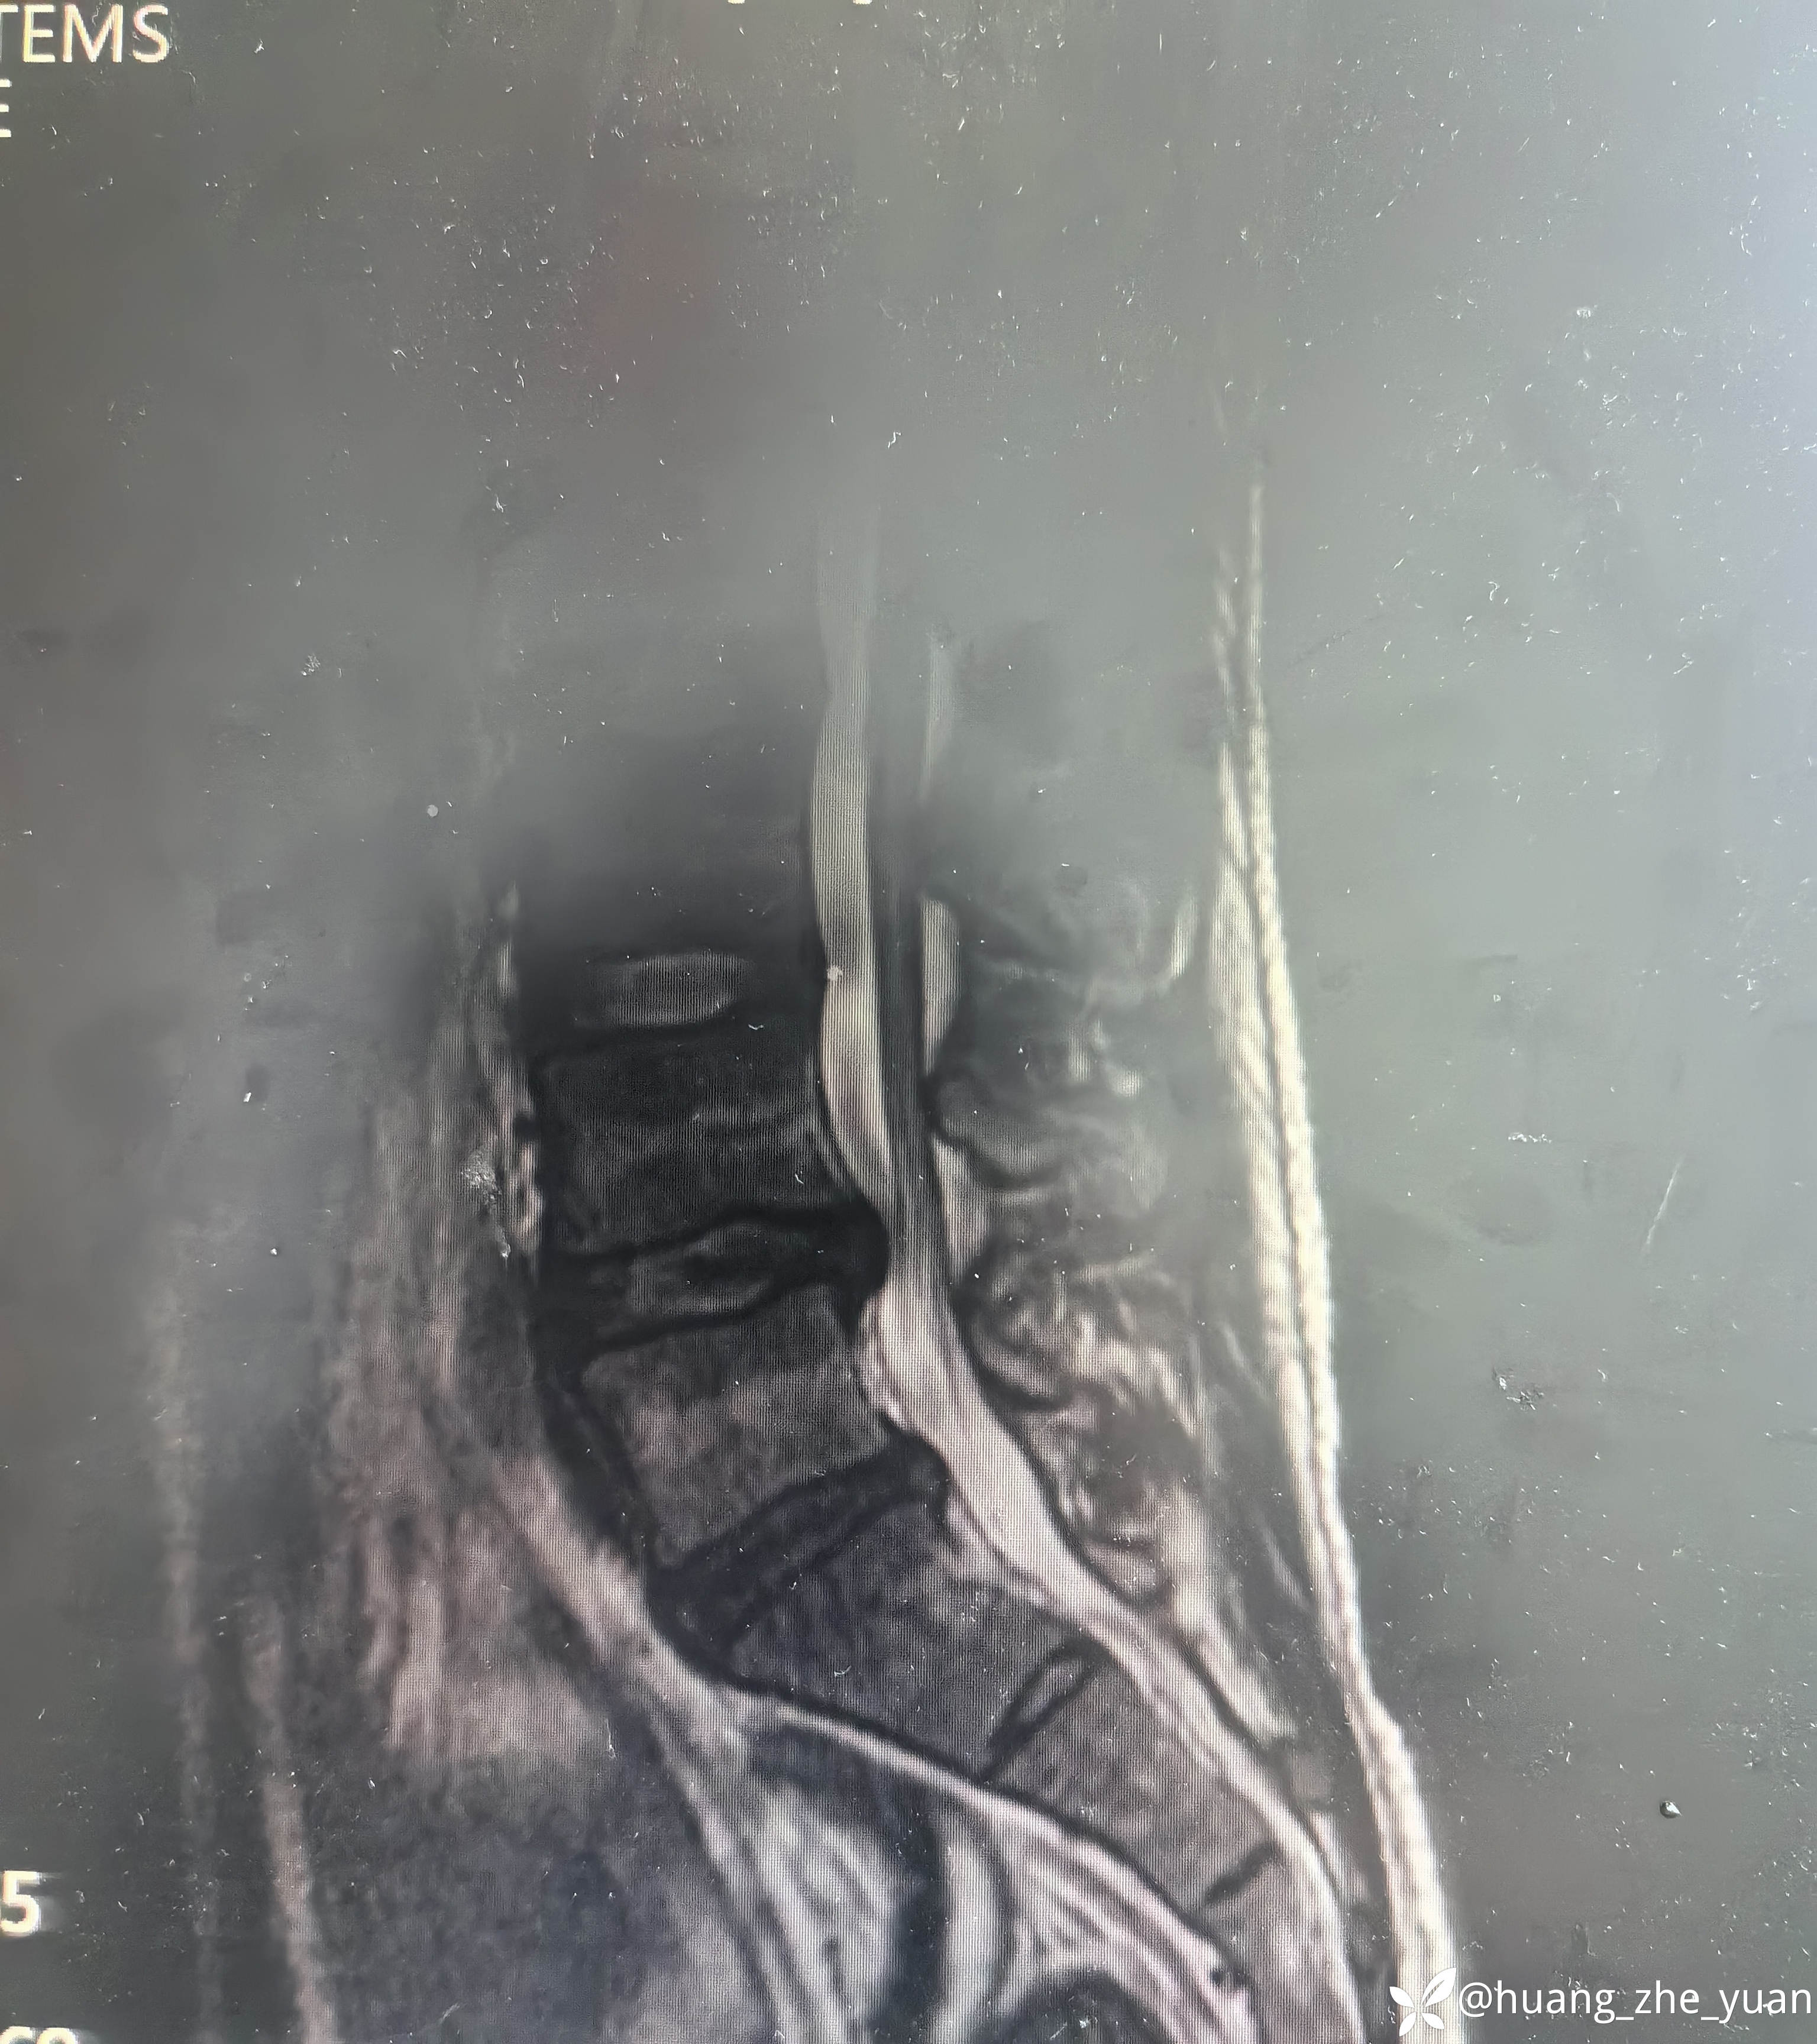

病人20岁,非常年轻,但是腰痛症状很明显,全天24小时无缓解,术前腰痛VAS评分7分,腿几乎不痛。保守治疗无效,融合又太早,和病人沟通后建议内镜下射频消融,术中尽量减少创伤。